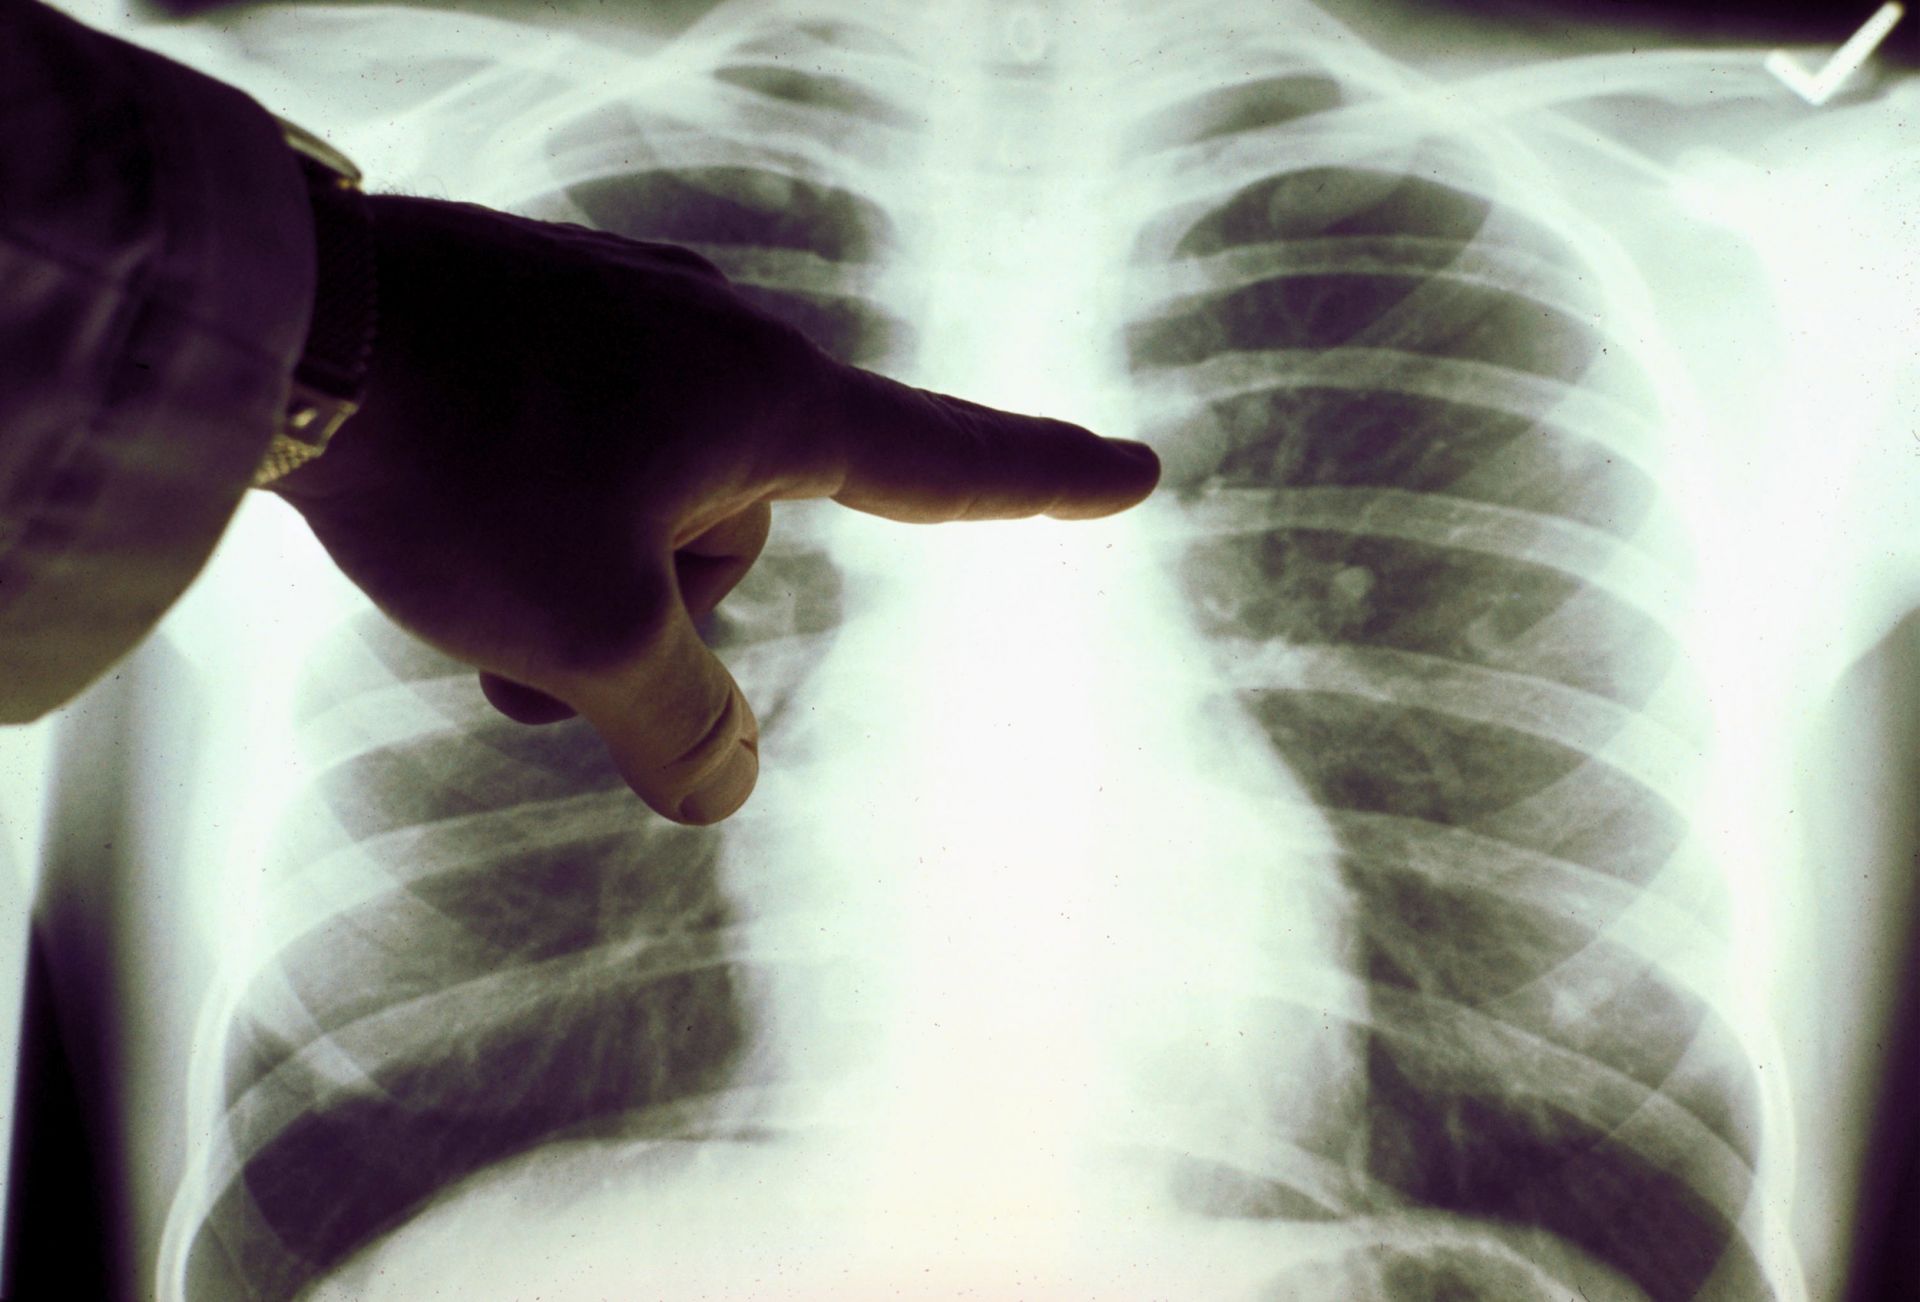

Καρκίνος του πνεύμονα: Αυτά είναι τα συμπτώματα που εμφανίζουν όσοι δεν καπνίζουν

Οι περισσότεροι μη καπνιστές δεν εκδηλώνουν πρώιμα σημάδια καρκίνου του πνεύμονα